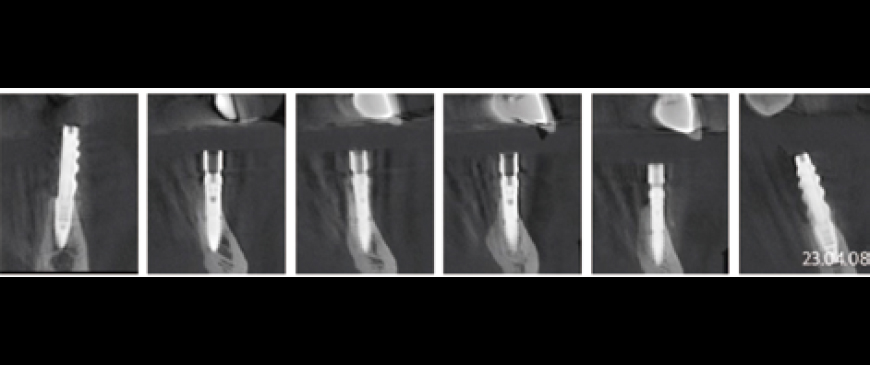

Fig 9

Post-surgery CBCT radiograph. All ARi implant threaded parts were properly positioned within the alveolar bone